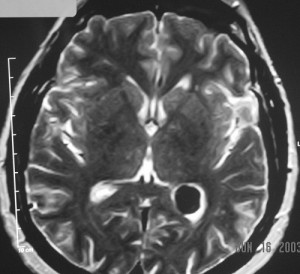

The images are a combination of T1 (before and after gadolinium enhancement), T2, and FLAIR pulse sequences in axial, sagittal and coronal sections of the patient’s brain (not all of the original images are in the monograph).

They reveal a 2cm mass in the trigone of the left lateral ventricle, centered within the choroid plexus. It has intermediate signal intensity on the pre-gadolinium T1WI, is hyperintense on the T2WI and enhances intensely and homogeneously after intravenous gadolinium administration. The mass is round, well-defined, has no mass-effects and does not invade the brain parenchyma. The ventricles are not dilated. The remainder of the brain is normal.